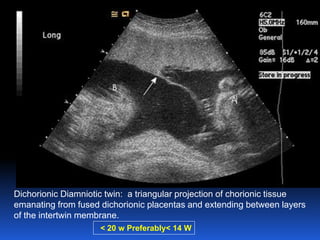

Dichorionic Diamniotic twin: a triangular projection of chorionic tissue

emanating from fused dichorionic placentas and extending between layers

of the intertwin membrane.

< 20 w Preferably< 14 W